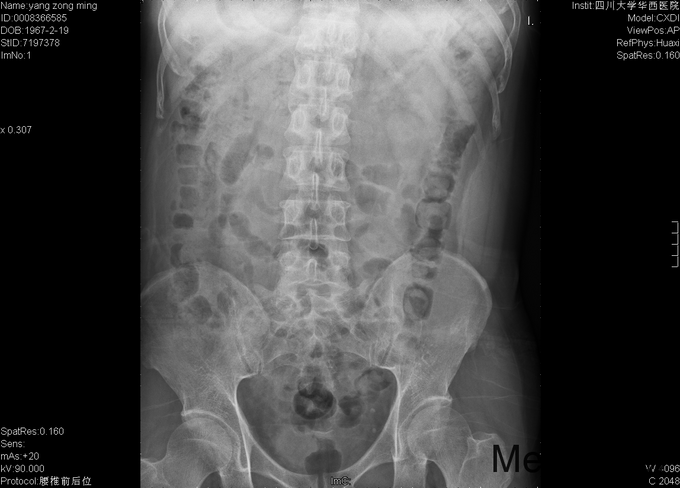

男,48岁8月,因“腰部疼痛伴右腿疼痛1+月”入院。患者1+月前出现腰部疼痛,伴右侧臀部、大腿后部、足背疼痛,大腿后部为主,不影响行走,不伴行走不稳、下肢麻木等,于外院行理疗、针灸等保守治疗,症状未见明显缓解。后症状有所加重,变换体位时疼痛加重,开始出现夜间痛醒,行走困难,遂至当地医院行靶点射频、封闭等治疗(具体不详),效果不佳,于2015-9-28入我院疼痛科,给予对症治疗(具体不详),症状有所缓解,现为进一步治疗入我科。

专科情况:视:双下肢等长,皮肤黏膜完整,无破损,双下肢肌肉无萎缩,脊柱外形正常。触:腰5-骶1棘突间压痛,腰部VAS疼痛评分5分,右下肢VAS疼痛评分6分,右下肢针刺觉减退。动量:四肢肌力、肌张力正常。右侧直腿抬高试验(+),加强实验(+),加强实验(-),双侧髌骨研磨试验(-)。生理反射均正常引出,病理征阴性。辅助检查:2015-9-29数字化X光腰骶椎正侧位摄影示:腰骶退行性病变、骨质疏松。数字化X光胸部正侧位摄影示:心肺未见明显异常。CT椎体一个部位骨三维成像扫描示:1、腰椎退行性病变,L5/S1椎间盘稍向右后突出2、骶管囊肿。MRI腰椎普通扫描示:1、L5/S1椎间盘突出2、腰椎退行性病变。

初步诊断:1、腰5骶1椎间盘突出症;2、骶管囊肿;3、骨质疏松。经皮内镜右侧椎间孔入路腰5骶1椎管减压+椎间盘髓核摘除+射频成形术